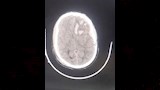

أعلنت مديرية الشئون الصحية بمحافظة الدقهلية، اليوم السبت، نجاح فريق طبي بمستشفى السنبلاوين العام في إنقاذ حياة مريض يبلغ من العمر 42 عامًا، بعد إصابته بنزيف حاد بالمخ وكسور بعظام الجمجمة نتيجة حادث طريق.

وقال بيان لمديرية الصحة بالدقهلية أن المريض قد وصل إلى استقبال المستشفى وهو يعاني من اضطراب شديد في درجة الوعي ونزيف من الأنف والأذن، وتم على الفور تقديم الإسعافات الأولية اللازمة وإجراء الفحوصات الطبية، التي أظهرت وجود كسور متعددة بالجمجمة ونزيف داخلي بالمخ وجرى حجز المريض بوحدة العناية المركزة، وبعد 6 ساعات من المتابعة الدقيقة، تبين زيادة حجم النزيف وتدهور مستوى الوعي، مما استدعى التدخل الجراحي العاجل.

وخلال العملية جرى رفع عظام الجمجمة لإزالة الانضغاط عن أنسجة المخ، وتكللت الجراحة بالنجاح، والمريض الآن تحت العلاج والمتابعة بالقسم الداخلي.